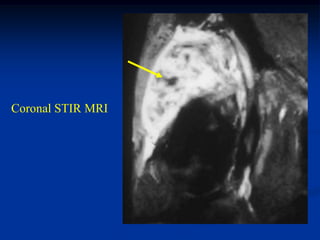

Case #253

29 year male

recent fracture ulna

18 months later

with desmoid tumor

at fracture site

Sagittal T-2 MRI 18 months later with desmoid tumor

Axial T-2 MRI at 18 months